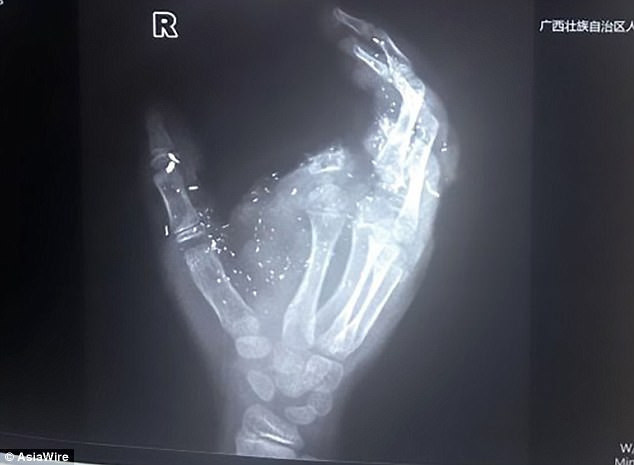

Çin'de 12 yaşındaki bir çocuk, şarj olurken telefonunun patlaması sonrasında sağ gözünü ve sağ elindeki işaret parmağını kaybetti. Guangxi eyaletindeki Meng Jisu adlı çocuk, cihaza ulaşmak için elini uzattığında, telefonu şarj ediyordu. Patlama, sağ elindeki işaret parmağını kopardı ve ablası onu kanlar içinde bulup ambulans çağırdığında bilinçsiz olarak yerde yatıyordu.

Çocuk daha sonra beş saatlik bir ameliyat geçirdi ve doktorlar saplanan parçaları yüzünden ve göğüs bölgesinden çıkardı. Keskin plastik parçalar doğrudan sağ gözüne saplandığından, 12 yaşındaki kız çocuğu kısmen kör kaldı.

Parmak, hastaneye götürülmediği için çocuğun sağ eline tekrar bağlanamadı, fakat götürülseydi de, doktorlar ciddi yaralanmalar yüzünden bunu yapmanın imkânsız olacağını söyledi.